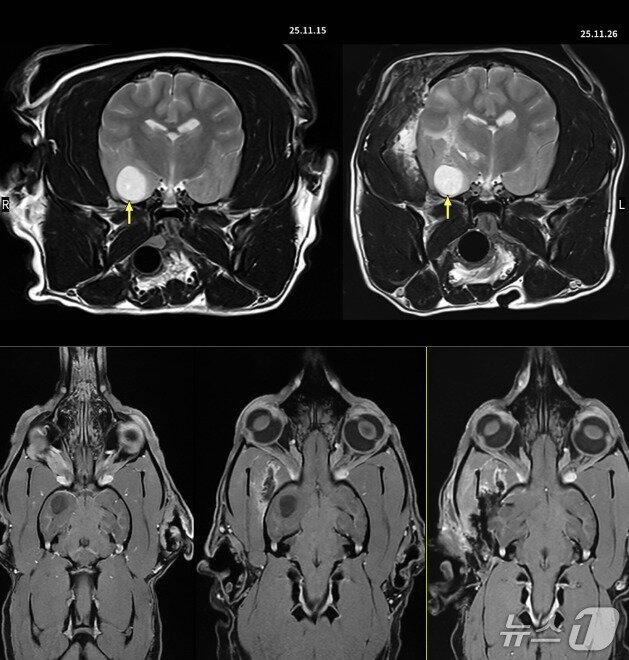

마비 증상 보인 푸들, 현미경 수술로 종양 제거뇌 수술을 받은 반려견(보호자 제공) ⓒ 뉴스1뇌 수술을 받은 반려견(이안동물신경센터 제공) ⓒ 뉴스1관련 키워드펫헬스케어동물최서윤 동물문화전문기자 한국동물병원협회, 수의대동물병원장협의회와 맞손…의료발전 모색해마루동물병원 인터벤션센터 개소 4주년…아이해듀, 25일 웨비나관련 기사피 섞인 기침하던 심장병 반려견…'골든타임'이 목숨 살렸다경기동물의료원, VECCS 레벨2 획득…"응급·중환자 케어 역량 인정"반려견 떡국부터 두쫀쿠까지…케이펫페어 대전, 체험 클래스 풍성줄 서듯 모여든 보호소 고양이들…어반포즈, 신제품 후원 나눔"입양동물 건강검진 신청하세요"…VIP동물의료센터-포인핸드, 협업